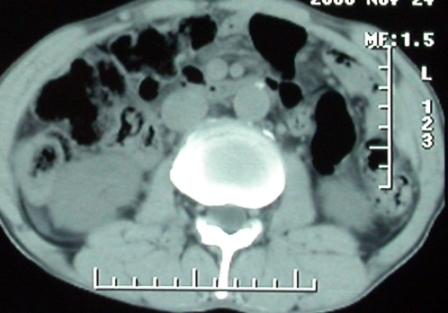

标题: CT5432:上腹隐痛、饱胀、消瘦2-月(尾状叶肝癌)。 [打印本页]

标题: CT5432:上腹隐痛、饱胀、消瘦2-月(尾状叶肝癌)。

男,57岁。

平扫